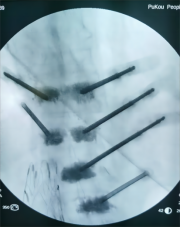

7. 复杂脊柱骨折内固定技术

随着区域内社会经济开发,复杂严重脊柱脊髓损伤病例增加,如何良好的手术治疗解除脊髓压迫、重建脊柱稳定性,使患者创伤最小、收益最大是促进患者康复至关重要的一环。性爱视频

已熟练开展各类脊柱损伤修复重建技术,每年完成复杂脊柱骨折手术处于区域领先水平。